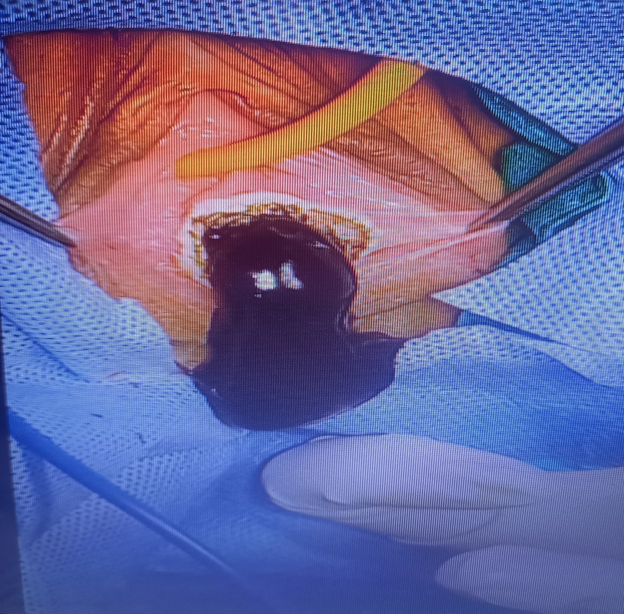

The patient underwent a hymenotomy and surgical drainage of the hematocolpos. A circular (annular) incision at the center of the bulging hymen was performed by electrocautery, followed by drainage of approximately 2500ml of thick brownish menstrual blood and diligent irrigation of the vagina (Figure 4). Care was taken to spare hymenal tissue circumferentially from the base in order to preserve virginity. A normal cervix was visualized and inspected. The vaginal entrance was surgically restored as follows: The edges of the vaginal margins were everted by suturing the inner vaginal mucosa to the exterior vestibular mucosa with absorbable No2 sutures, firstly by performing single interrupted sutures which were then followed by a purse-string suture (Figure 5). Vaginal swabs were collected and the results of the cultures were negative for infection. A penrose tube was placed at the introitus to ensure unimpeded continuous drainage and was removed on the second postoperative day. Broad-spectrum antibiotics were administered for post-operative chemoprophylaxis. The postoperative course was uncomplicated and the patient was discharged on the fourth postoperative day. Her wound had completely healed by the time she had her three-month post-op follow-up appointment (Figure 6). To this day, she has been experiencing normal painless menses.

Figure 5 Placement of sutures at vaginal margins.